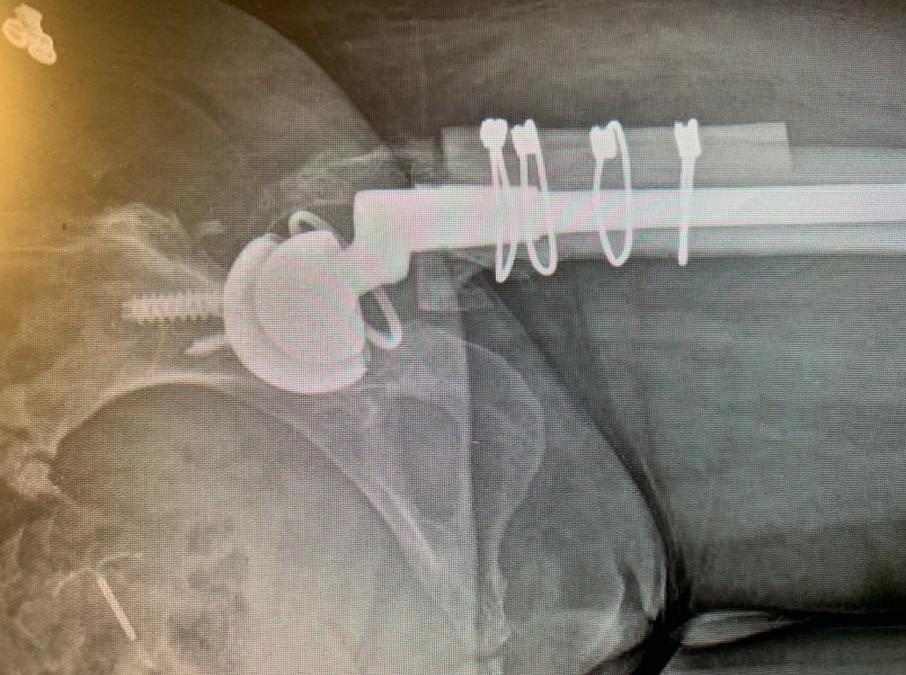

La paciente es una mujer de 75 años que acudió a nosotros con dolor intenso en la cadera izquierda tras someterse a una fijación interna de reducción abierta (ORIF) de la cadera izquierda. El paciente vino con radiografías para revisar, como se muestra a continuación,...